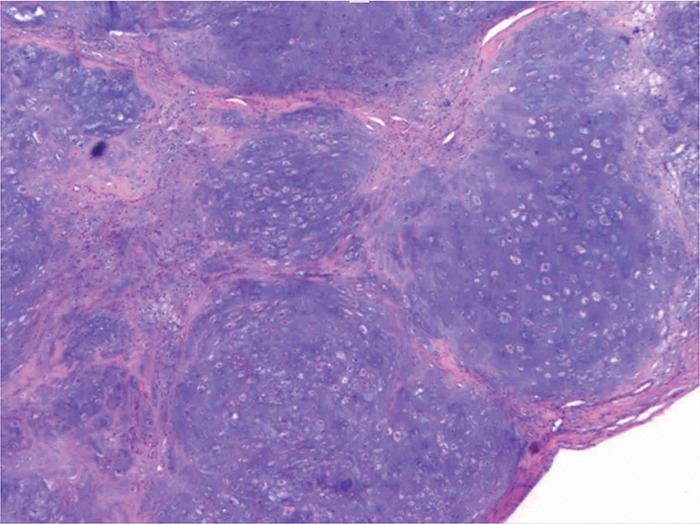

教学要点:骨膜软骨瘤是一种罕见的软骨瘤类型,其特征是骨膜下,钙化的软组织肿块压迫皮质骨,不累及髓腔。

Teaching point: Periosteal chondroma is a rare type of chondroma characterized by a subperiosteal, calcified soft tissue mass that compresses the cortical bone and does not involve the medullary cavity.